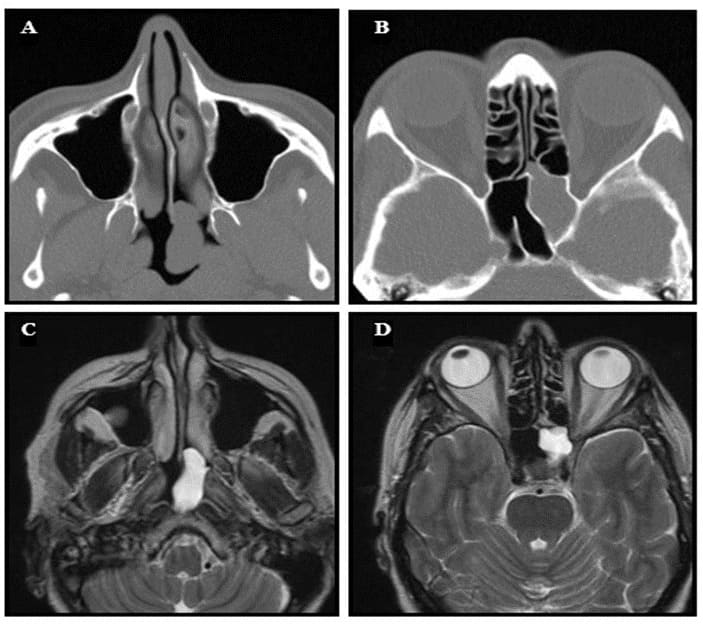

A sphenochoanal polyp is a rare form of a choanal polyp originating from the sphenoid sinus and extending to the choanae through the sphenoethmoidal recess. Far less common than the antrochoanal polyp, the sphenochoanal polyp originates from the sphenoid sinus itself or from the sphenoid ostium. Endoscopic surgery is indicated to relieve the nasal obstruction (19-21).

Figure 10: A case of a sphenochoanal polyp. (A) Axial CT-scan showing an opacity in the nasopharynx. (B) Axial CT-scan showing opacity of the left sphenoid sinus. (C) T2-weighted axial MRI showing homogeneous opacity of the polyp in the nasopharynx. (D) T2weighted axial MRI showing a hyperintense lesion in the sphenoid sinus.